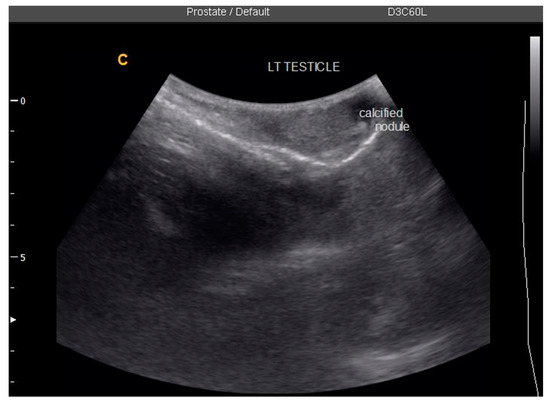

| 3 | 49 | 1 | 6 | N/D # | Left testicular nodule and mild bilateral hydroceles |

| 49 | Eggs in urine, semen; no real-time PCR done | Left testicular nodule, mild bilateral hydroceles | No eggs in urine or semen; negative PCR | Bilateral hydroceles |